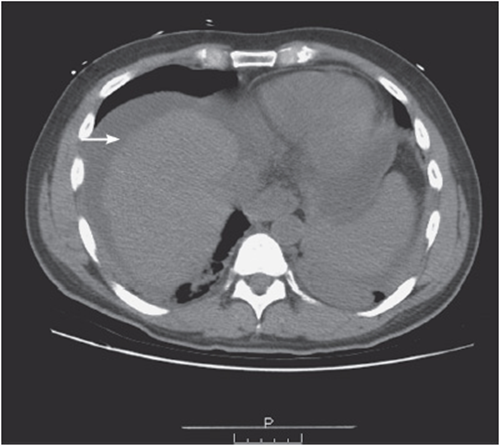

• Look for subcapsular hematomas or liver lacerations in trauma (see Figure 56-5), and for liver nodules in a patient with a history of malignancy.

Figure 56-5. Splenic laceration caused by a motor vehicle crash.

vi. Check the spleen:

• Check for lacerations (eg, trauma), enlargement (malignancy, hyper-splenism), or abnormal fluid collections (eg, liver abscess or cyst) (see Figure 56-6).

Figure 56-6. Liver fluid collection suspicious for liver abscess.